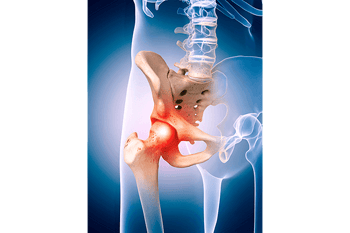

Hip Problems

Hip Problems The hip is one of the most common joints to suffer from arthritis and degeneration! This is due to the hip being a heavily utilized weight-bearing joint. Most hip problems can avoid risky surgery if they are dealt with early and properly. The hip...